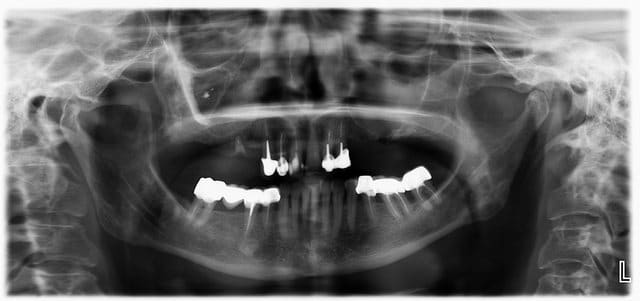

1°)_Bridge antérieur 13/23 avec fraisages et attachements + stellite posterieur

2°)_Extraction + 6 implants + mise en charge immédiate + Branemark

3°)_Bridge anterieur 13/23 + sinus lifts droit et gauche + 3 implants de chaque coté

Patiente 58 ans. En bonne santé (physique et financière). Son souhait : quelque chose qui dure et sur lequel elle ne reviendra pas...

3 sans hésiter (je ne vois pas grand chose sur la pano, trop petite sur mon écran)

Il faut, si on choisi la solution double sinus-lift, faire "vider" le sinus droit avant.

Au scanner, il est complètement obstrué certainement à cause du bout de pâte ou autre que l'on peut apercevoir sur la pano.

La question à 15k€, pourquoi elle a perdu ses dents? Ça commence un peu en bas aussi non, la paro sur molaires ?

Manque bcp d'info pour proposer un plan global

58 ans et condition dentaire très limite...

Retro du bas : les bridges tiennent car pas d'antagoniste ?

Scan sinus

Paro pas bonne. Quid des dents du bas et de l'occlusion?